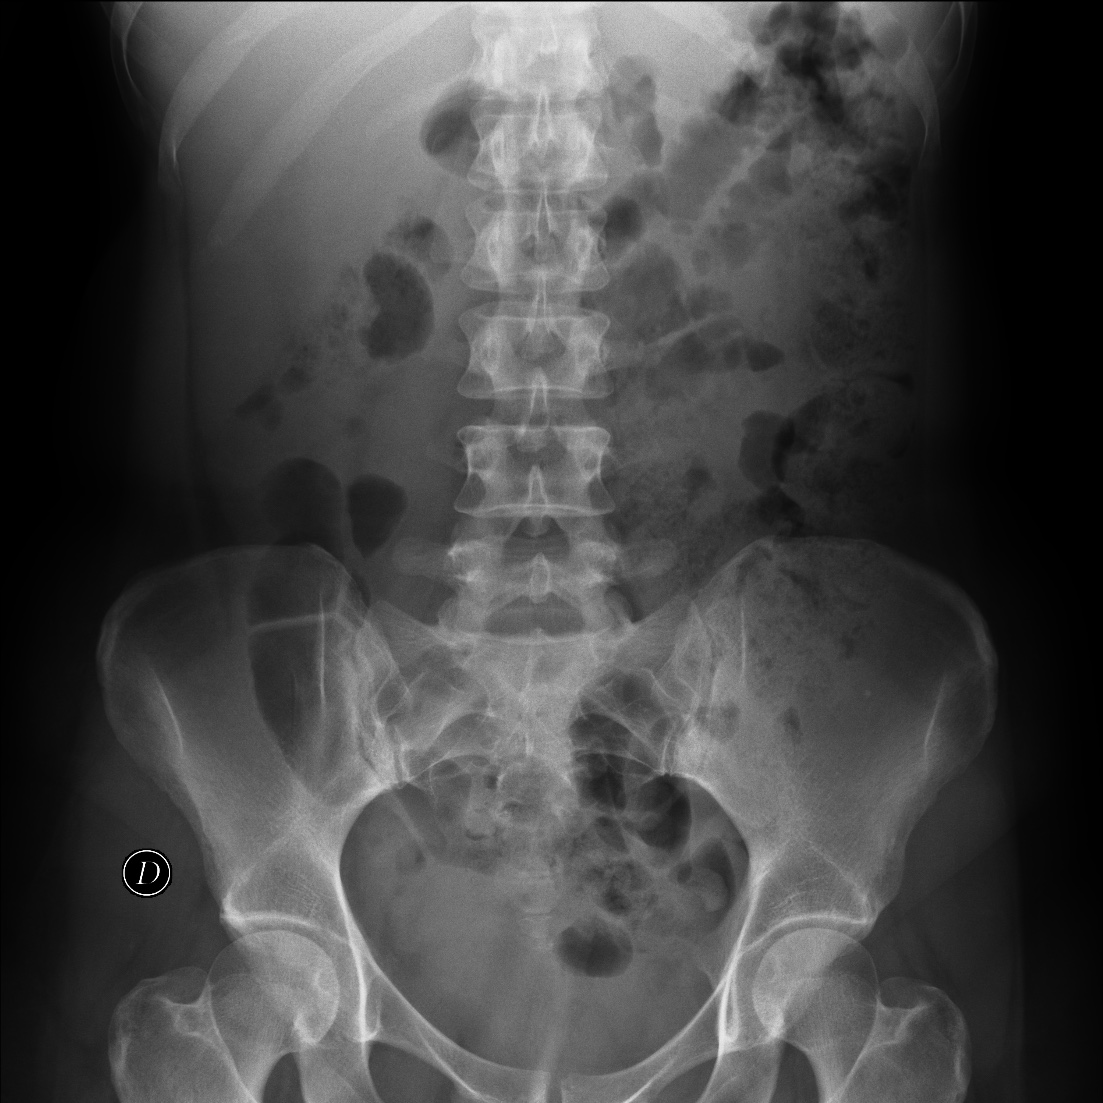

La radiografía y la ecografía de abdomen no aportaron hallazgos de significación patológica.

Es un estudio barato y se realizaba de rutina previamente a la obtención de una urografía excretora. Hoy en día no es necesaria de rutina y se ha sustituido por el Scout de los TC en prácticamente todas las instituciones. Se podía observar gas o calcificaciones, pero existen numerosos fallos debido al gas intestinal y no visualización de las calcificaciones del tracto urinario o la confusión con los procesos transversos de las vértebras.